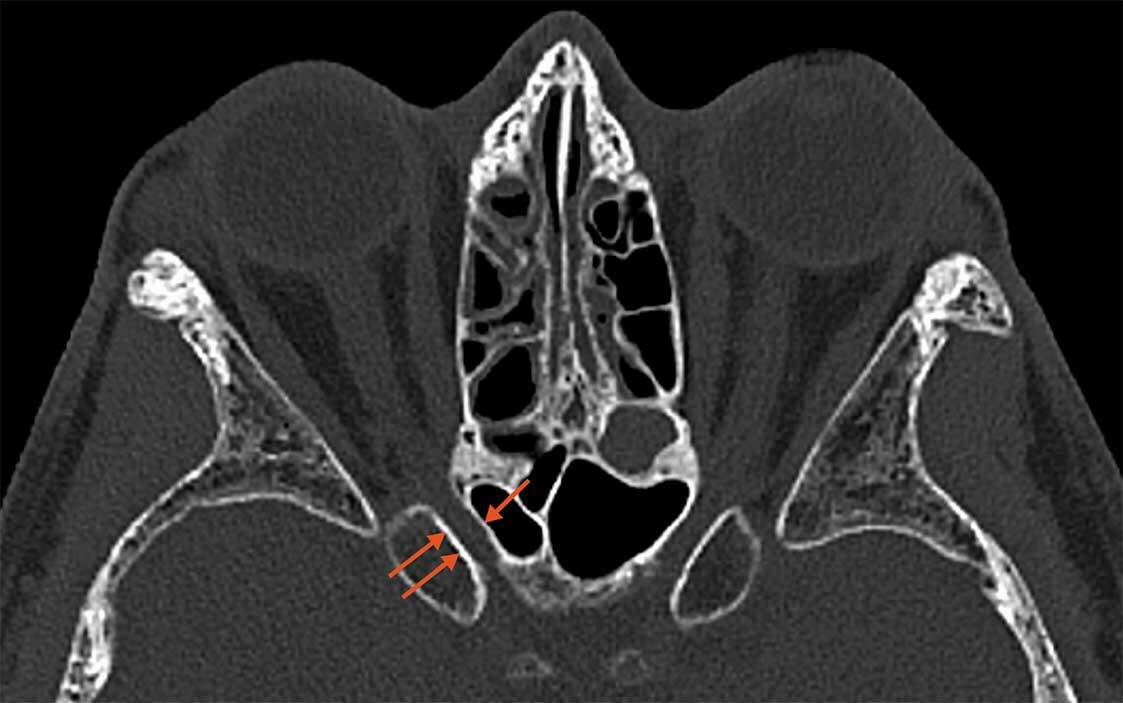

Figure 2. Schisis maculaire myopique en imagerie OCT ultra grand champ objectivant l’adhérence pathologique du vitré, avec des tractions exercées sur les vaisseaux rétiniens (tête de flèche), et l’étirement de la rétine externe maculaire associé à un détachement fovéolaire (flèche).